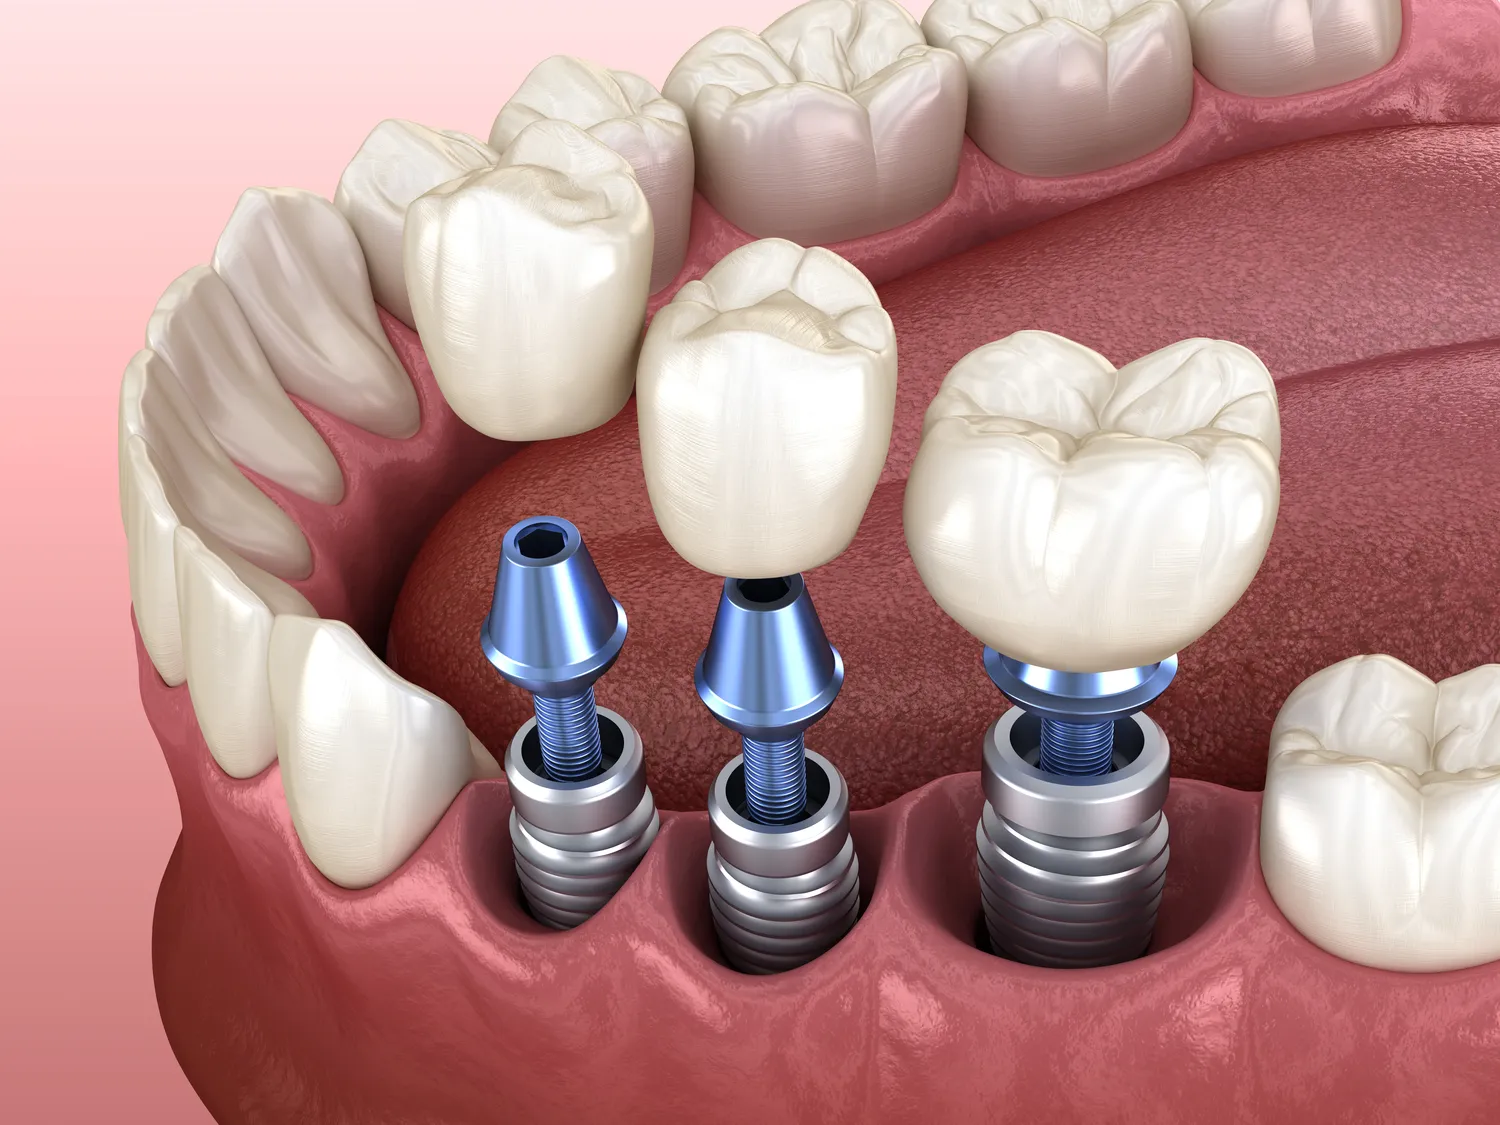

W ostatnich latach implantologia zębowa w Szczecinie zyskała na znaczeniu dzięki wprowadzeniu nowoczesnych technologii, które znacznie poprawiają jakość leczenia oraz komfort pacjentów. Jednym z najważniejszych osiągnięć jest zastosowanie cyfrowych technologii w planowaniu zabiegów. Dzięki skanowaniu 3D oraz programom komputerowym lekarze mogą dokładnie zaplanować miejsce wszczepienia implantu, co minimalizuje ryzyko komplikacji i zwiększa precyzję zabiegu. Dodatkowo, technologia CAD/CAM pozwala na szybkie i precyzyjne wykonanie koron czy mostów protetycznych, co skraca czas oczekiwania na ostateczny efekt leczenia. Inną innowacją są implanty o zwiększonej biokompatybilności, które lepiej integrują się z kością pacjenta, co przekłada się na ich dłuższą trwałość. Warto również wspomnieć o technikach regeneracyjnych, takich jak przeszczepy kości czy zastosowanie membran, które umożliwiają odbudowę tkanki kostnej przed wszczepieniem implantu.

Proces zakupu implantu zęba w Szczecinie jest wieloetapowy i wymaga staranności zarówno ze strony pacjenta, jak i lekarza. Pierwszym krokiem jest konsultacja stomatologiczna, podczas której specjalista ocenia stan uzębienia oraz ogólny stan zdrowia pacjenta. Na podstawie przeprowadzonych badań diagnostycznych, takich jak zdjęcia rentgenowskie czy tomografia komputerowa, lekarz może zaplanować odpowiednią strategię leczenia. Następnie pacjent zostaje poinformowany o kosztach związanych z zabiegiem oraz dostępnych opcjach finansowania. Po zaakceptowaniu planu leczenia następuje etap przygotowawczy, który może obejmować ekstrakcję zębów lub regenerację kości. W dniu zabiegu lekarz wszczepia implant w odpowiednie miejsce w szczęce lub żuchwie. Po zakończeniu procedury pacjent otrzymuje zalecenia dotyczące pielęgnacji oraz diety na czas rekonwalescencji. Ostatnim etapem jest montaż korony protetycznej, która przywraca pełną funkcjonalność i estetykę uzębienia.